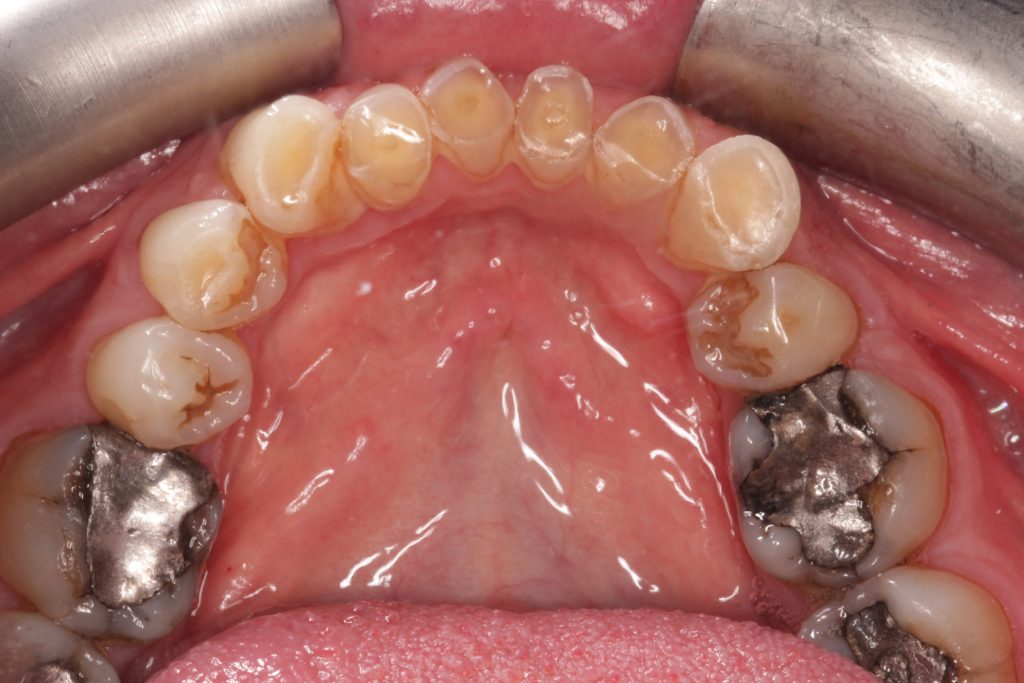

Other challenges

- Alveolar compensation, maintaining occlusal vertical dimension (OVD)

- Shortened clinical crowns with pulp exposure imminent on lower anteriors

- Asymmetrical gingival zeniths

- Buccally positioned canines.

Treatment plan

- Surgical Crown lengthening of upper 2-2